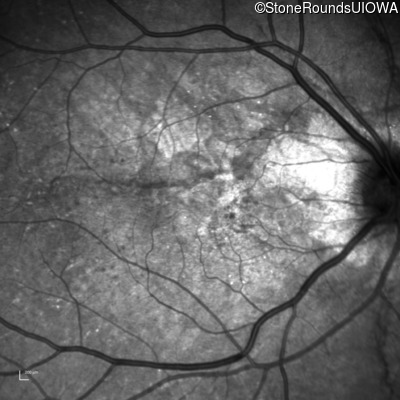

Infrared Fundus Photograph - Right - 20/25 +1

Exemplar